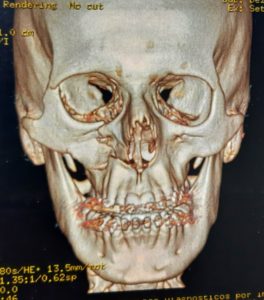

O diagnóstico é feito pelo exame físico dos ferimentos e, nos casos de suspeita de fratura, deve se associar radiografias e tomografias computadorizadas. Esse avaliação poderá ser feita no hospital (se o paciente estiver internado) ou no consultório odontológico. O primeiro passo no tratamento é garantir a vida do paciente. O profissional deve garantir que o paciente esteja respirando bem e sem lesões graves que podem levar a morte rapidamente (como hemorragias severas, obstrução de vias aéreas e lesões de órgãos vitais)

A maioria dos ferimentos simples na pele pode ser tratada com anestesia local, limpeza da lesão e sutura. As fraturas da face e lesões complexas são tratadas sob anestesia geral. Os ossos quebrados são restaurados utilizando-se, geralmente, mini-placas e parafusos de titânio (que são biocompatíveis e não sofrem rejeição) que facilitam a recuperação e cicatrização óssea e dos tecidos